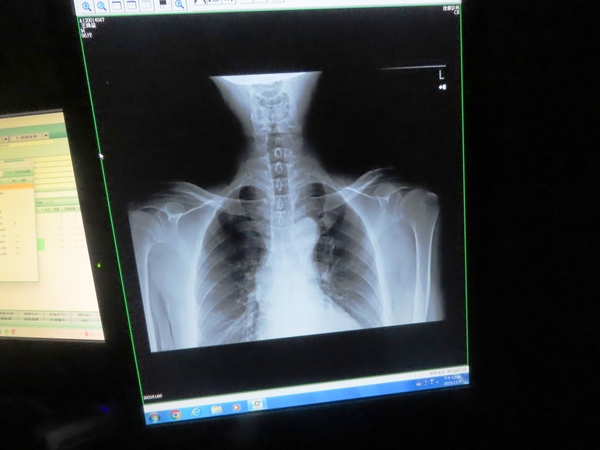

10:43 左手不能抬高,來佳德診所 (臺北市松山區健康路18號) 求診

佳德診所看診室

原來肩部活動與頸部脊椎有關

肩夾擠症候群(Shoulder Impingement Syndrome)是指當您抬高手臂時,肩膀的旋轉肌袖肌腱或肩峰下滑囊在肩峰(肩膀上方的骨頭凸起)下方被夾擠到,導致疼痛和發炎的現象。

左肩膀打了兩針 (大概是類固醇)